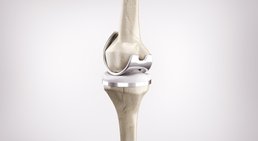

Mein fachärztlicher Schwerpunkt liegt in der Behandlung des Kniegelenks. Durch die internationale Ausbildung an einer Knieklinik, aktive Mitgliedschaft in zahlreichen wissenschaftlichen Fachgesellschaften sowie langjährige Erfahrung führe ich auch komplexe Knieoperationen (u.a. Meniskustransplantation) und Kombinationseingriffe in höchster Fallzahl in Wien durch.